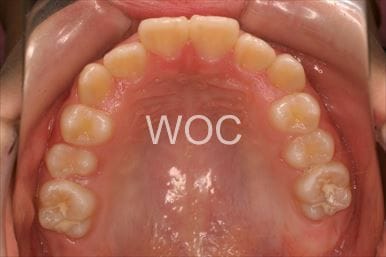

治療後1

治療後2

治療後3

治療後4

治療後5

- 年齢:22歳女性

- 主訴:出っ歯、前歯で噛み切れない

- 基本矯正料金:85万円

- 治療期間:1年4ヶ月

- 非抜歯